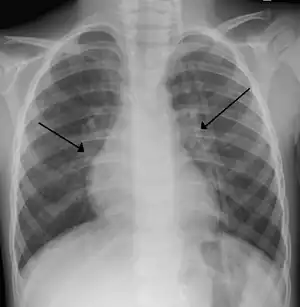

| An X-ray of a child with RSV showing the typical bilateral perihilar fullness of bronchiolitis. | |